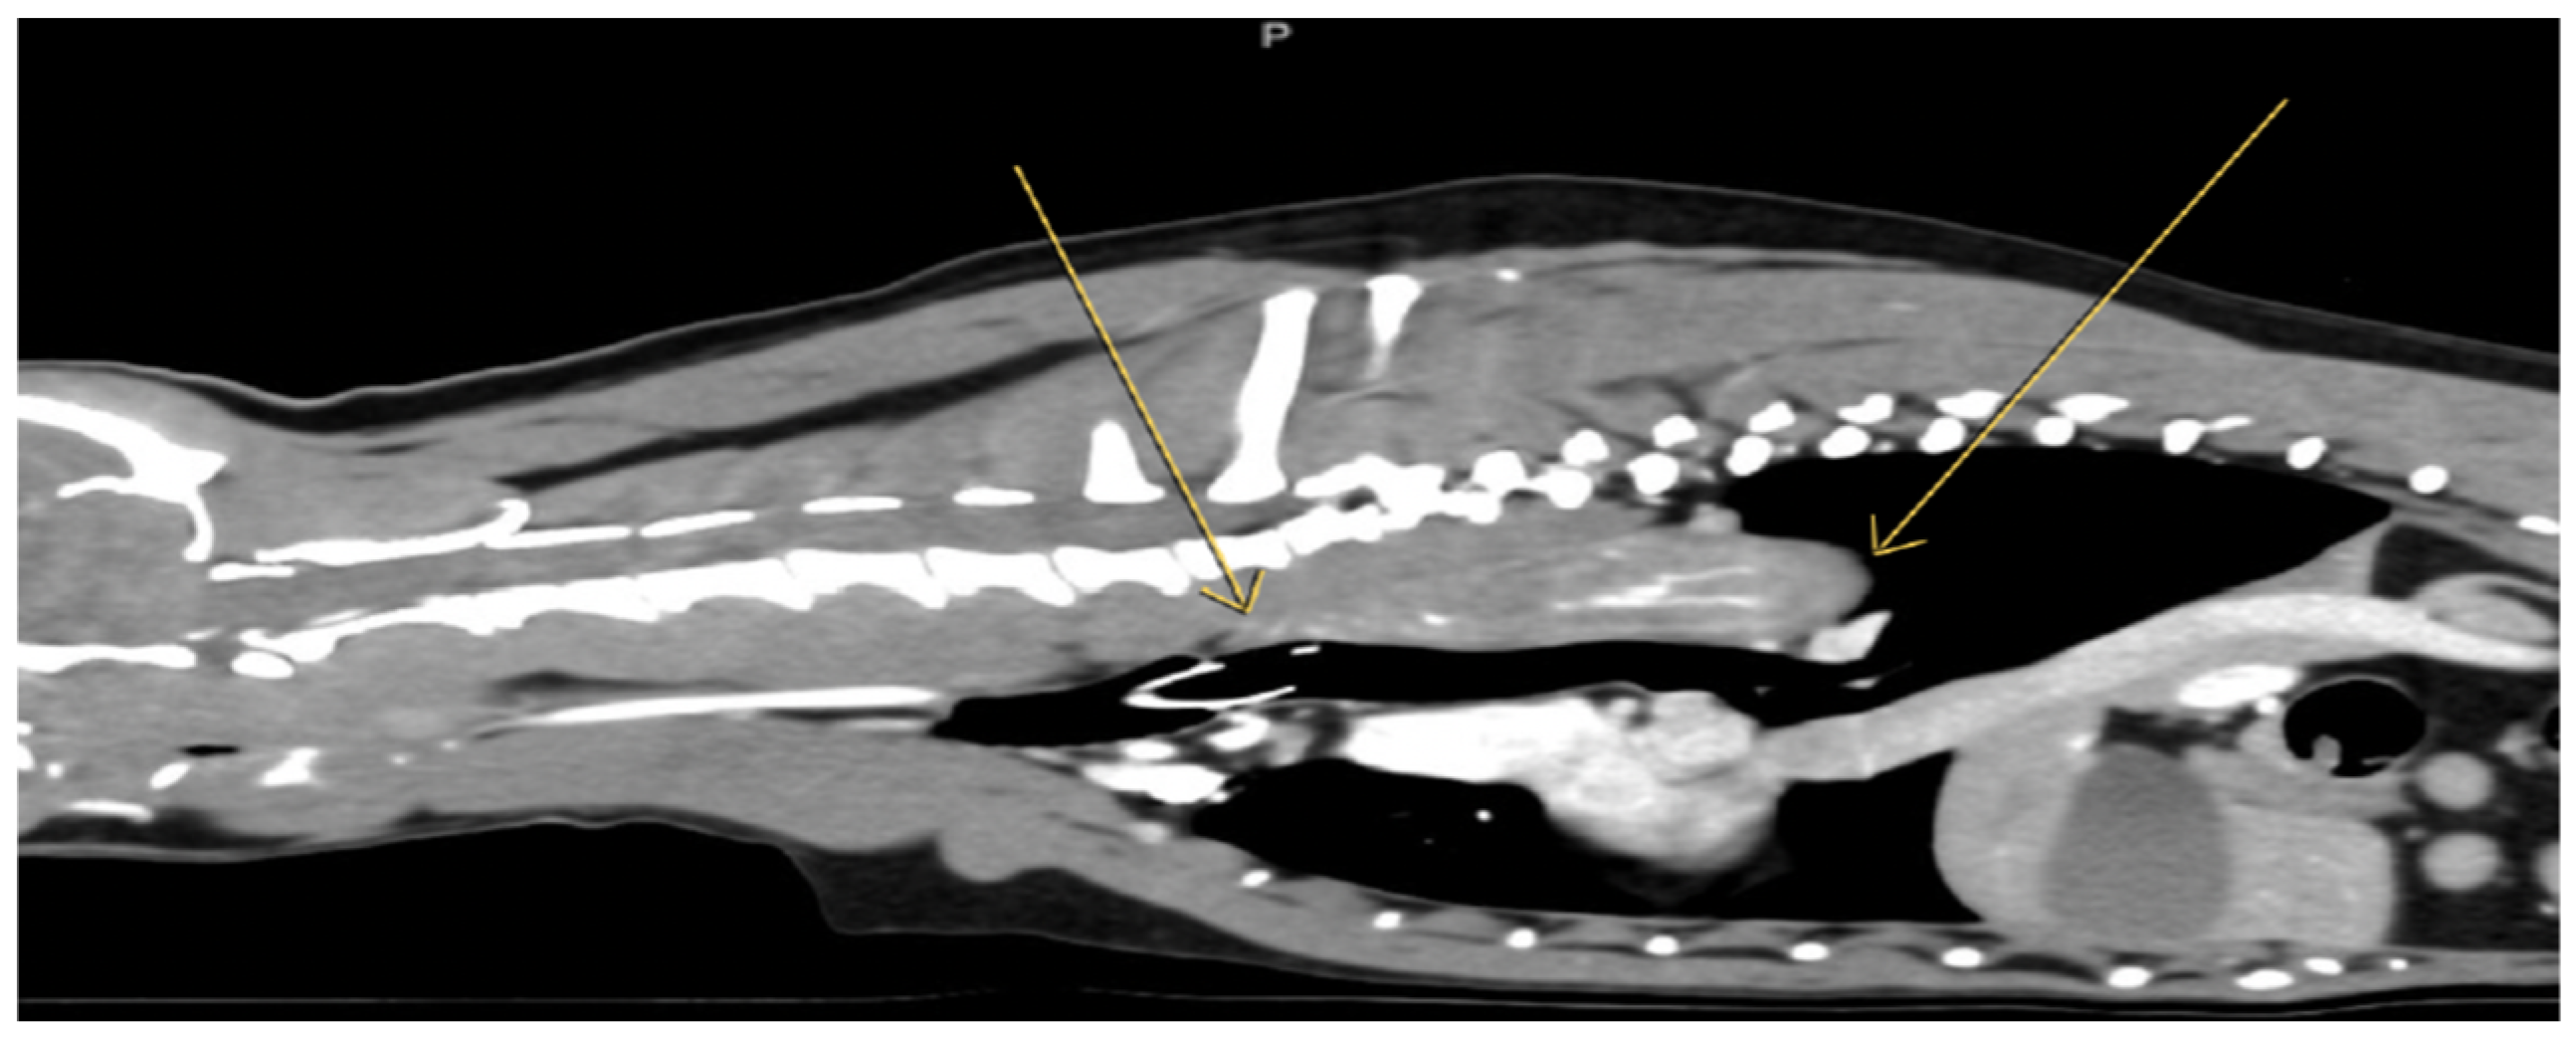

Figure 4.

Esophageal lesion on sagittal view in computed tomography. The yellow arrows indicate an asymmetrical ductal lesion of the esophagus with spindle-shaped projection in its lumen, soft tissue density, about 7 cm in the longitudinal axis with a high central and peripheral vascularity after intravenous injection of the contrast agent, extending from Th1 to Th7 is noted. A mildly controlled collection of air into the esophagus and mild left axillary lymphadenopathy were detected.